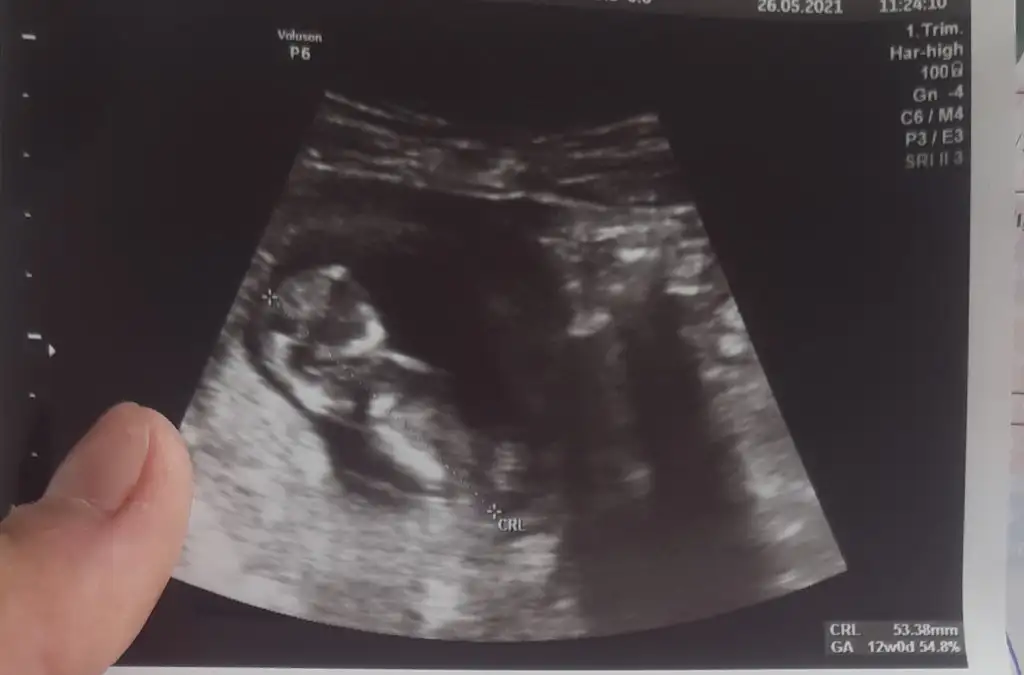

Bana da bakar misiniz ilki 6+4 vajinal diger ikisi 12+5 karindan cinsiyet belli degil henuz tahmin ederseniz sevinirim